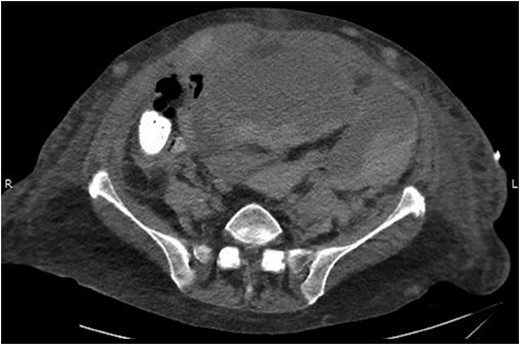

On examination she was pale, had a blood pressure of 97/52 mm Hg and heart rate of 74. On abdominal examination, she was distended and tender in all four quadrants. Her hemoglobin (Hb) was 4.7 g/dl, white blood cell count was 11.4 × 109/l and platelet count was 146 × 103/mcl. Her international normalized ratio (INR) was 1.5, which was reversed effectively with two units of fresh frozen plasma. She was transfused five units of packed cells improving her hemoglobin from 4.7 to 7.8 g/dl. An emergency contrast CT scan of abdomen and pelvis was performed which showed a large right-sided RSH extending into the space of Retzius (Fig. 1).

The following day the patient’s urine output declined progressively and she subsequently developed acute renal failure. A urinary catheter was placed but significant resistance was encountered secondary to her locally distorted anatomy from the hematoma. A repeat non-contrast CT abdomen and pelvis was therefore obtained which showed further extension of the RSH into the space of Retzius with retroperitoneal extension causing hydronephrosis (Fig. 2).

Abdominal CT scan showing the RSH extending into space of Retzius and retroperitoneum.